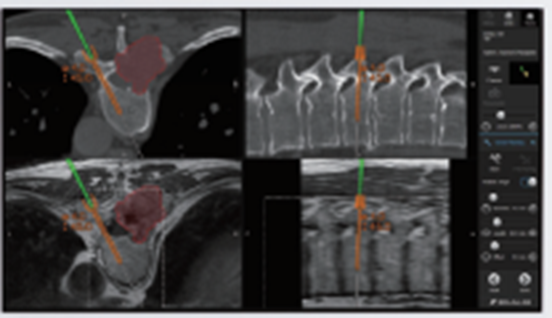

【Spine ARナビゲーション】